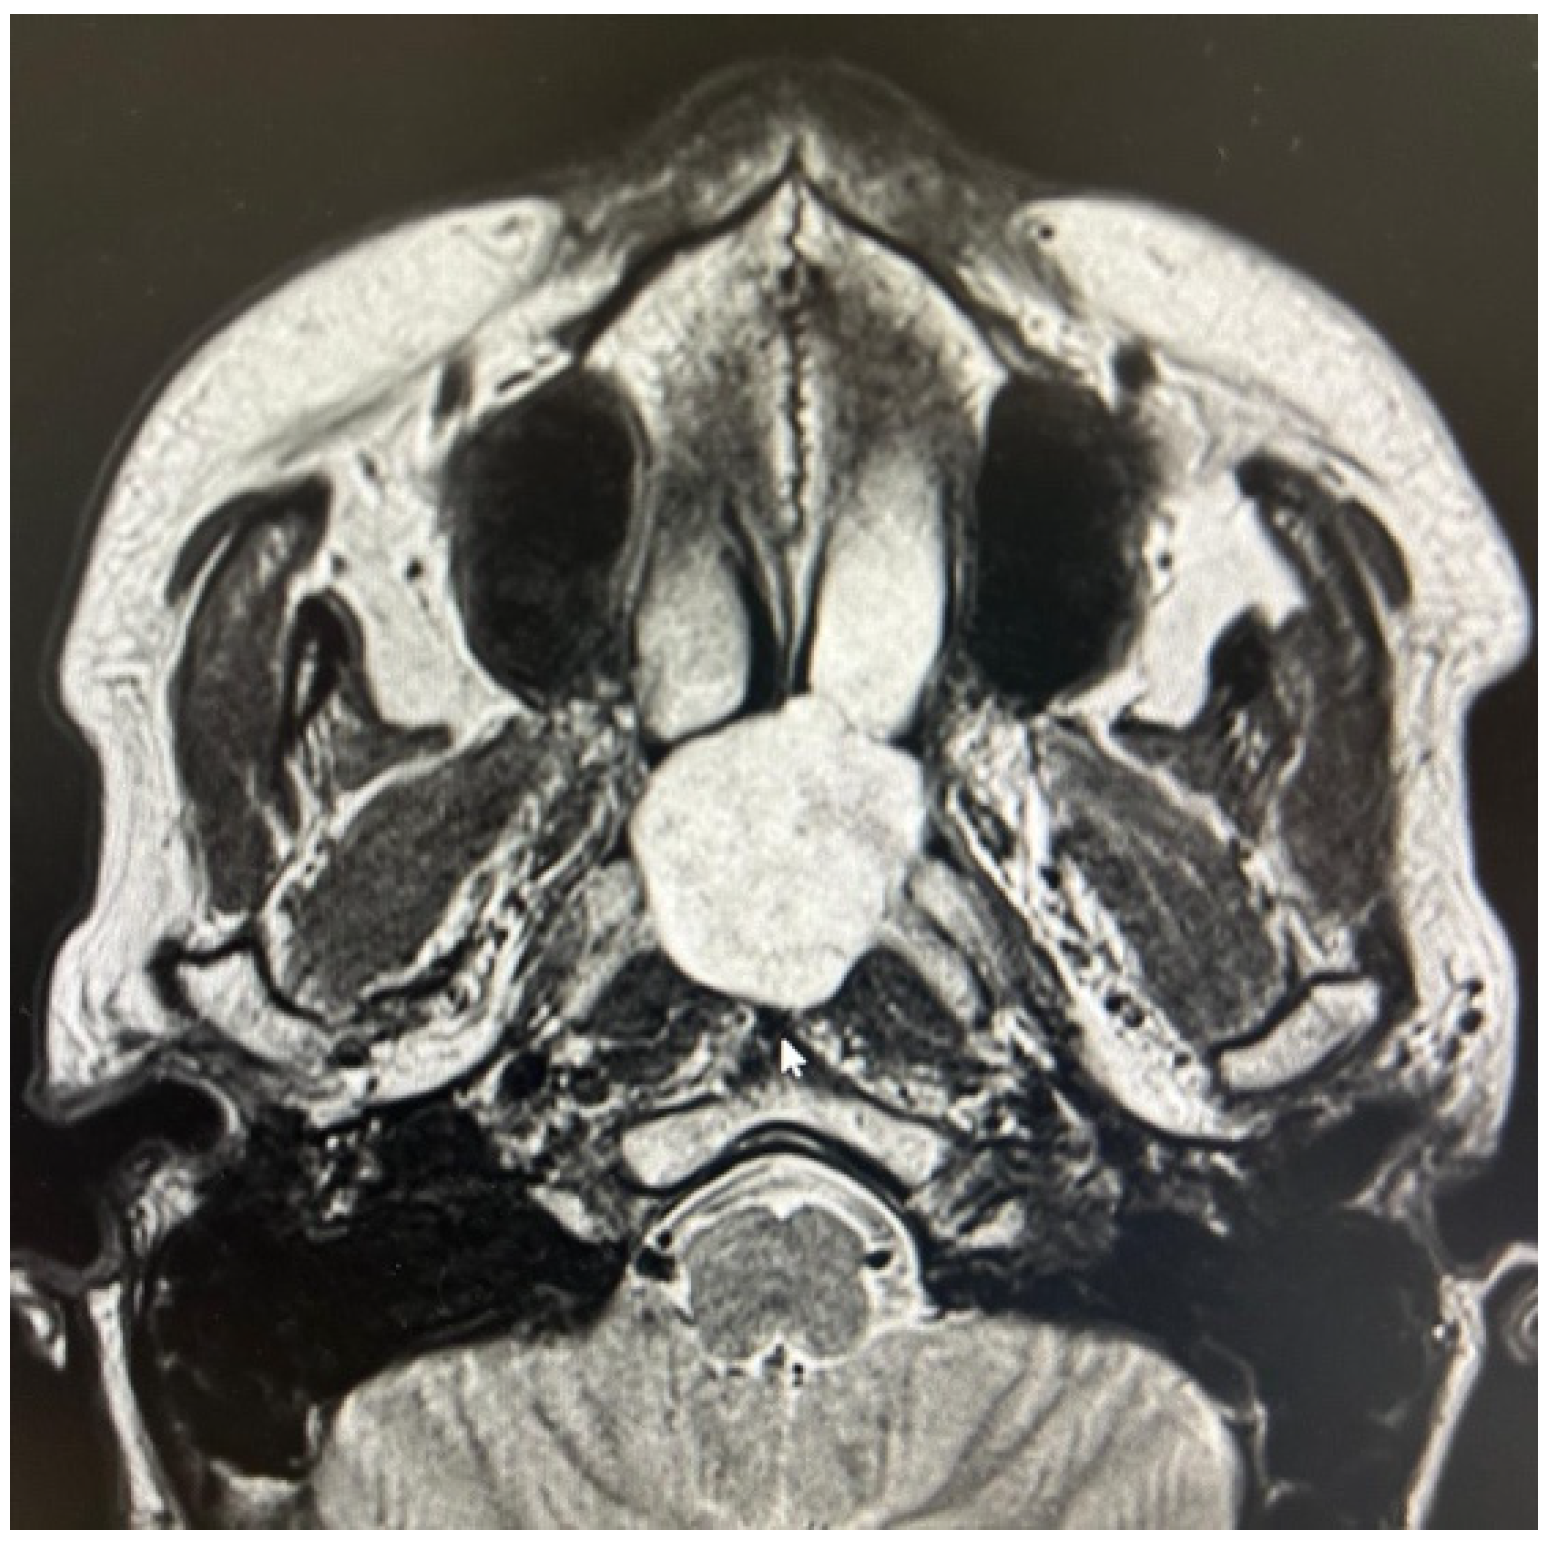

The other two true PPS lesions, an ectopic thyroid gland and a lipoma, also presented with a favorable displacement pattern, with the major vessels situated posteriorly to the lesions. Regarding the two remaining parapharyngiomas, which were schwannomas of the cervical sympathetic chain, the transoral approach was feasible only due to an atypical displacement pattern. Despite originating from the carotid space, the major vessels exhibited a posterior displacement rather than the anterior displacement typically expected with lesions of the carotid space (Figure 4). Consideration should be given to the preservation of neural and vascular structures within the PPS. It is imperative to safeguard major vascular structures, such as the internal carotid artery and internal jugular vein, particularly since injury to the internal carotid artery during a transoral approach could lead to catastrophic outcomes. Indeed, in our case series, no damage to these major vessels has ever occurred. However, regarding neurogenic lesions originating from the carotid space, a distinct consideration applies to schwannomas. As these tumors originate from nerves, even if the nerve of origin can be preserved during resection, this does not guarantee the preservation of its function [1,12,13,14]. In our presented case series, for instance, two cases of schwannoma originating from the sympathetic chain resulted in Horner’s syndrome. Therefore, accurate radiological diagnosis of PPS lesions, especially those within the carotid space, is crucial for guiding the surgeon regarding the nerve of origin. Nevertheless, it must be highlighted that schwannomas do not always exhibit a typical pattern of vascular or neural displacement, and our case series serves as an illustrative example of this variability.

Figure 4. PPS schwannoma showing atypical posterior major vessels displacement.